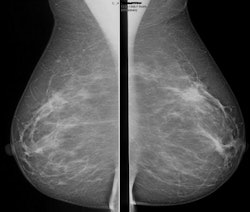

Kuhl and colleagues investigated whether a streamlined protocol, consisting only of the first postcontrast subtracted images and their maximum intensity projection (MIP) reconstructions, would be suitable for screening purposes. The idea was to trade some of the high sensitivity of breast MRI for acquisition and interpretation speed, with a long-term goal of increasing access to breast MRI by reducing the cost associated with the examination, according to Kuhl.

Kuhl and colleagues tested the protocol in a population of 443 women at increased risk of breast cancer who had undergone 606 breast MRI screening studies. Images were read by experienced breast radiologists who were asked to first review the MIPs and search for significant enhancement, and then to evaluate the first postcontrast subtracted images for any further categorization. (The first postcontrast subtracted images show the change in image due to contrast; MIP is a volume rendering method for 3D data.)

After the radiologists had read images produced with the streamlined protocol, they then analyzed the full diagnostic breast MRI protocol. Kuhl's group then compared the diagnostic yield and accuracy of the streamlined readings versus that of the full protocol.

Kuhl's team found that the average time required to read MIPs was 2.8 seconds, while 28 seconds were required for the postcontrast subtracted images. Patient setup consumed the rest of the time required for the three-minute protocol. A total of 11 breast cancers were diagnosed, for an additional yield of 18.2 cancers per 1,000 women.

Of these cancers, four were ductal carcinoma in situ (DCIS) and seven were invasive, with a median size of 8 mm. All were intermediate or high grade. The streamlined protocol detected nine (82%) of the 11 cancers; specificity of the protocol was the same as that of the full protocol, at 94.4%. The streamlined protocol had 33 false-positive diagnoses, versus 35 for the full procedure.

The negative predictive value of the streamlined protocol was 99.6%, compared with 99.8% for the full protocol, according to the researchers.